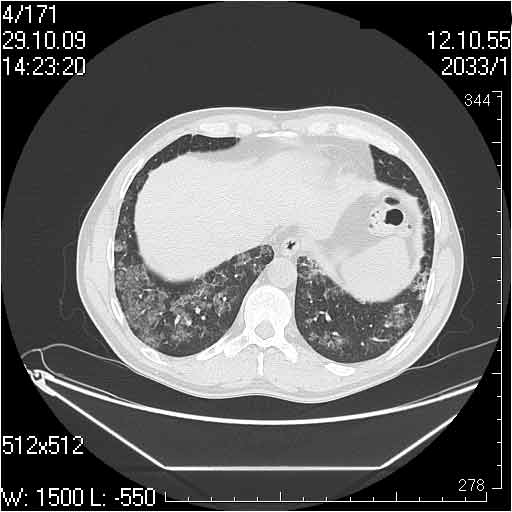

Случай №3

Женщина 51 год

Случай 3:смешанные изменения; подходят для интерстициальной пневмонии, тактика аналогична случаю 1.